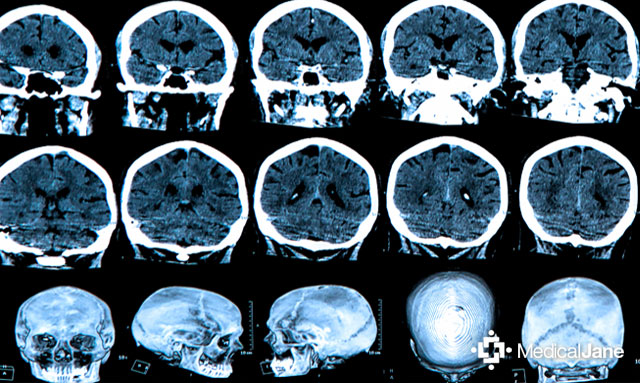

Dr. Hergenrather has commented extensively on the anti-cancer potential of cannabis. At the Marijuana for Medical Professionals Conference in September 2014, he remarked that cannabinoids “kill cancer in many and most cases”, specifically mentioning effectiveness against colon cancer and skin cancer. He also discussed a glioma remission, achieved solely with cannabis oil, in the cannabis journal O’Shaughnessy’s.

Even patients from other countries are seeking out Dr. Hergenrather’s assistance. Lindsay Carter, an Australian teenager with a glioma tumor, has repeatedly traveled to the United States to undergo cannabis extract therapy. The treatment proved effective at shrinking his tumor, but upon returning to Australia and losing access to cannabis oil, the tumor began growing again.